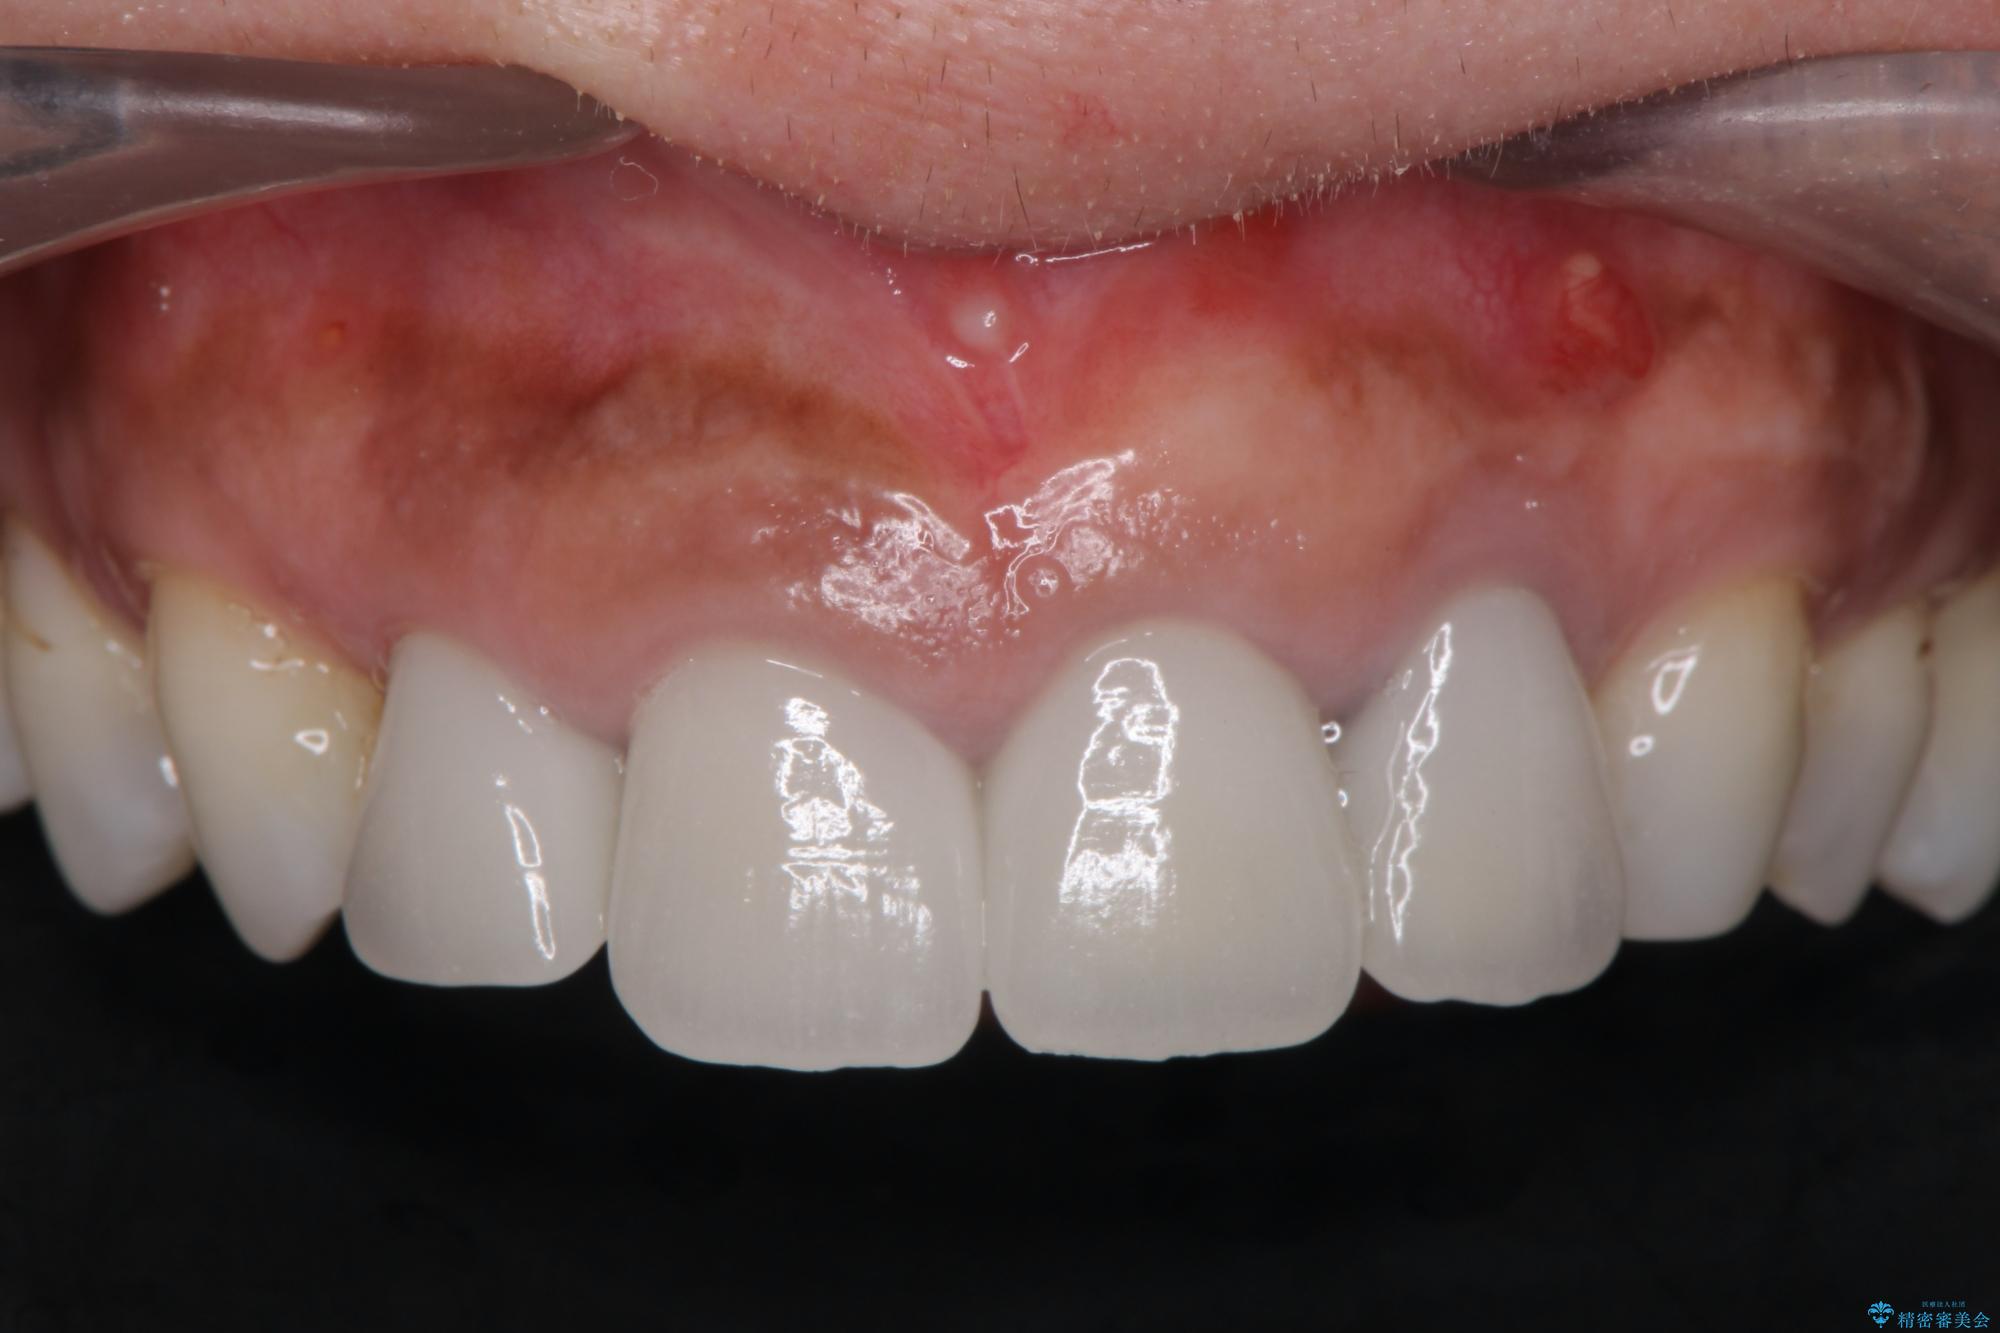

治療前

歯槽堤保存術を併用したブリッジ治療 治療前画像 歯槽堤保存術を併用したブリッジ治療 治療前画像 歯槽堤保存術を併用したブリッジ治療 治療前画像 歯槽堤保存術を併用したブリッジ治療 治療前画像 歯槽堤保存術を併用したブリッジ治療 治療前画像 歯槽堤保存術を併用したブリッジ治療 治療前画像 歯槽堤保存術を併用したブリッジ治療 治療前画像 歯槽堤保存術を併用したブリッジ治療 治療前画像 歯槽堤保存術を併用したブリッジ治療 治療前画像 歯槽堤保存術を併用したブリッジ治療 治療前画像